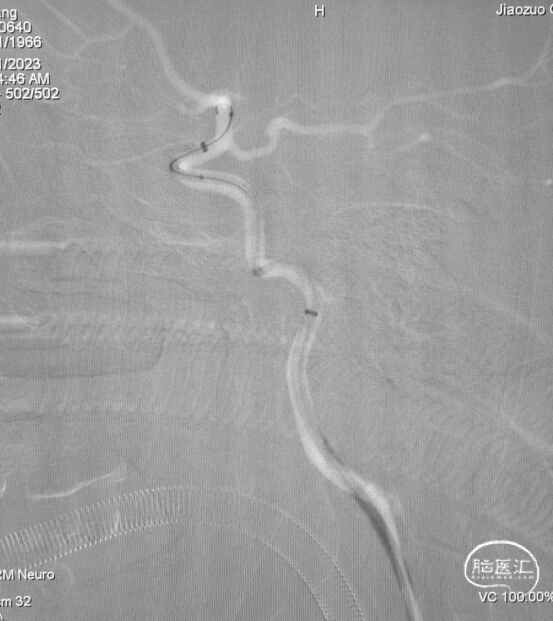

6F心玮吞川®颅内血栓抽吸导管行基底动脉血栓抽吸。

复查造影示基底动脉及其分支显影良好,取栓装置中可见白色胶冻状血栓。